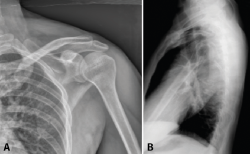

Figura 3. Radiografías anteroposterior (A) y lateral (B).

Presentamos el caso de un varón de 35 años, cerrajero de profesión y diestro. Sin antecedentes medicoquirúrgicos de interés. Sufre una caída desde un andamio de aproximadamente 2 metros de altura. Como resultado, es diagnosticado de una fractura de escápula en varios fragmentos, fractura del sexto arco costal derecho y una fractura no desplazada del ala sacra derecha. Las imágenes de la radiografía simple, de la TC y su reconstrucción 3D se muestran en las Figuras 3, 4 y 5.